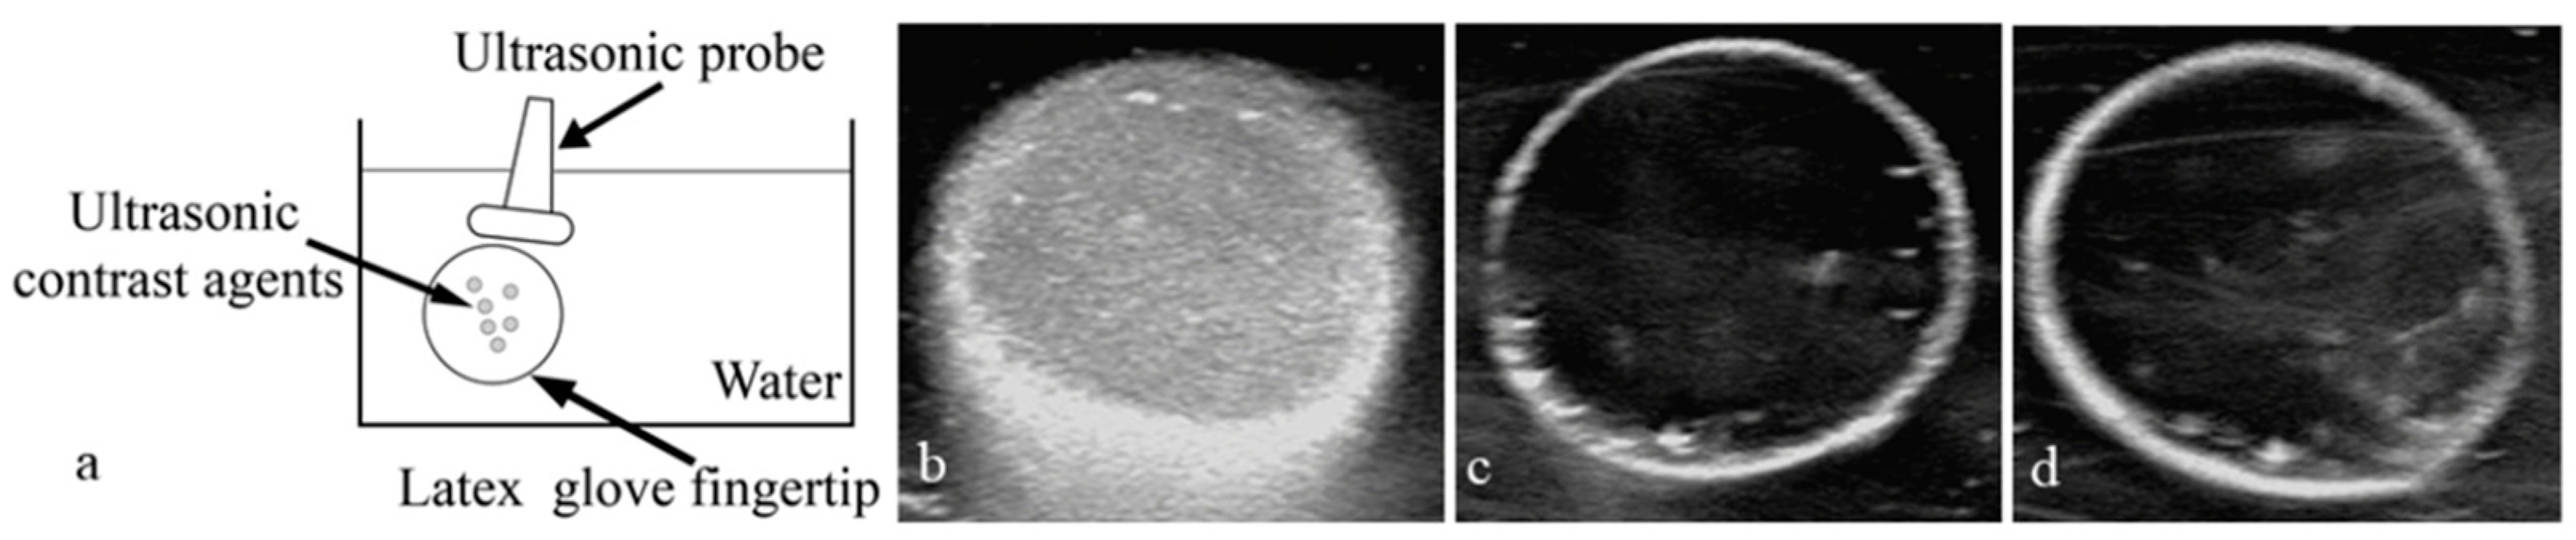

3.7. Echogenicity of Nanoparticles In Vitro at 37 °C

3.8. Application of Nanoparticles in Ultrasound-Enhanced Imaging of Tumors